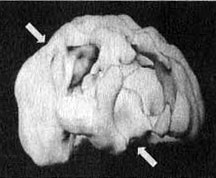

Мозг Эллен — последствия инсульта ![]() Трехмерное изображение поверхности мозга, вид слева. Обратите внимание на обширную «дыру», сформировавшуюся в результате инсульта в левой лобной доле 2. SPECT позволяет дать точную оценку состояния пациента, позволяющую предотвратить, заболевание в будущем. Нэнси, 59 лет, страдала от тяжелой депрессии, не поддававшейся лечению. Поступила в психиатрическую лечебницу, где ей было проведено исследование SРЕСТ. Каково же было мое удивление, когда оказалось, что в прошлом, при полном отсутствии соответствующих симптомов, она перенесла два обширных инсульта. Таким образом, стало понятно, что вызвало эту депрессию, не поддававшуюся обычному лечению. У 60 % пациентов, перенесших кровоизлияние во фронтальных долях, через год развивается тяжелая депрессия. Получив результаты SPECT, я немедленно проконсультировался с неврологом, который постарался определить причины инсультов, к которым нередко приводят, скажем, бляшки в сонных артериях или сердечная аритмия. Он пришел к выводу, что причиной инсультов у Нэнси стали тромбы, и назначил ей препараты, снижающие вязкость крови, чтобы предотвратить развитие новых инсультов. Мозг Нэнси — последствия двух инсультов ![]() Трехмерное изображение поверхности, вид сверху ![]() Трехмерное изображение поверхности, вид справа 3. С помощью SPECT можно получить информацию, помогающую врачу добиться понимания и сострадания к пациенту у членов его семьи. Фрэнк — состоятельный, хорошо образованный человек. Вскоре после того как ему исполнилось 70 лет, он стал забывчивым. Сначала он забывал мелочи, но со временем провалы в памяти стали прогрессировать, и он начал забывать значимые факты собственной биографии: где он живет, как зовут его жену и даже как зовут его самого. Жена и дети были не в состоянии понять, чем вызваны такие перемены, а его рассеянность и забывчивость их нередко раздражали. Результаты SPECT показали, что у Фрэнка на всей поверхности мозга отмечается резкое снижение активности, и особенно во фронтальных, париетальных и височных долях. Это была классическая картина синдрома Альцгеймера. Показав семье снимки и объяснив, что забывчивость Фрэнка имеет четкую физиологическую природу, я помог им осознать, что он не специально раздражает их, а серьезно болен. Впоследствии, вместо того чтобы упрекать его за забывчивость, близкие Фрэнка стали поддерживать его и разработали схемы, позволившие эффективнее бороться с трудностями, возникающими у всякого, кто вынужден жить рядом с человеком, страдающим болезнью Альцгеймера. Мозг Фрэнка — болезнь Альцгеймера ![]() Трехмерное изображение поверхности, вид сверху ![]() Трехмерное изображение нижней поверхности Обратите внимание на выраженное общее снижение активности, особенно в париетальных долях (см. стрелки, рис. слева) и в височных долях (см. стрелки, рис. справа). 4. SPECT позволяет проводить дифференциальную диагностику состояний со сходной симптоматикой. Я познакомился с Маргарет, когда ей было 68. Выглядела она неухоженно и неопрятно. Маргарет жила одна, и ее близких это очень беспокоило, так как у нее появились симптомы тяжелой деменции. После того как она чуть не сожгла дом, оставив включенной плиту, ее поместили в психиатрическую клинику, где в то время работал я. Из общения с ее близкими обнаружилось, что Маргарет часто забывала, как зовут ее собственных детей, и нередко, ведя машину, сбивалась с дороги и оказывалась в незнакомом месте. Водительские навыки ухудшились настолько, что после четырех небольших ДТП всёго за шесть месяцев у нее отобрали права. К тому времени, когда я встретился с ее близкими, многих из них эта ситуация уже утомила, и они были готовы сдать Маргарет в специализированный приют. Другие были против такого решения и хотели бы сначала обследовать ее в условиях стационара. На первый взгляд казалось, что Маргарет страдает болезнью Альцгеймера. Однако по результатам SPECT обнаружилось, что активность мозга в париетальных и височных долях не нарушена. Если бы у нее был синдром Альцгеймера, кровоток в этих областях должен был бы быть снижен. Вместо этого единственной патологией, которую нам удалось обнаружить на снимках SPECT, стала зона повышенной активности в глубокой лимбической области в центре мозга. Такая картина часто наблюдается у пациентов, страдающих депрессией. Из-за схожей симптоматики у больных старшего возраста нередко бывает трудно дифференцировать депрессию и болезнь Альцгеймера. Тем не менее при псевдодеменции (депрессии, которая выглядит как слабоумие) человек может выглядеть слабоумным, на самом деле таковым не являясь. Это чрезвычайно важный момент, так как, диагностировав болезнь Альцгеймера, мы даем близким ряд специальных рекомендаций и назначаем пациенту некоторые медикаментозные средства. Между тем, диагностируя депрессию, мы проводим агрессивную медикаментозную терапию антидепрессантами в сочетании с психотерапией. Результаты обследования Маргарет убедили меня в том, что ей следует назначить антидепрессант Wellbutrin (бупропион). Всего три недели спустя она уже была разговорчивой, ухоженной и охотно общалась с другими пациентами. Через месяц после госпитализации ее выписали домой. Перед выпиской она попросила меня написать письмо в автоинспекцию с просьбой вернуть ей водительские права. Поскольку мы с ней ездим по одному и тому же шоссе, я заколебался. Я сказал ей, что, если улучшение будет стойким и сохранится на протяжении по меньшей мере полугода, а сама она станет придерживаться рекомендаций врача и принимать все лекарства, я напишу письмо в автоинспекцию. Через полгода она оставалась в хорошей форме. Я сделал повторный SPECT — результаты показали полную норму. Тогда я обратился в автоинспекцию, и ей вернули права. Мозг Маргарет — псевдодеменция ![]() Трехмерное изображение снизу — активный мозг, до лечения. ![]() Трехмерное изображение снизу активный мозг, после лечения. |